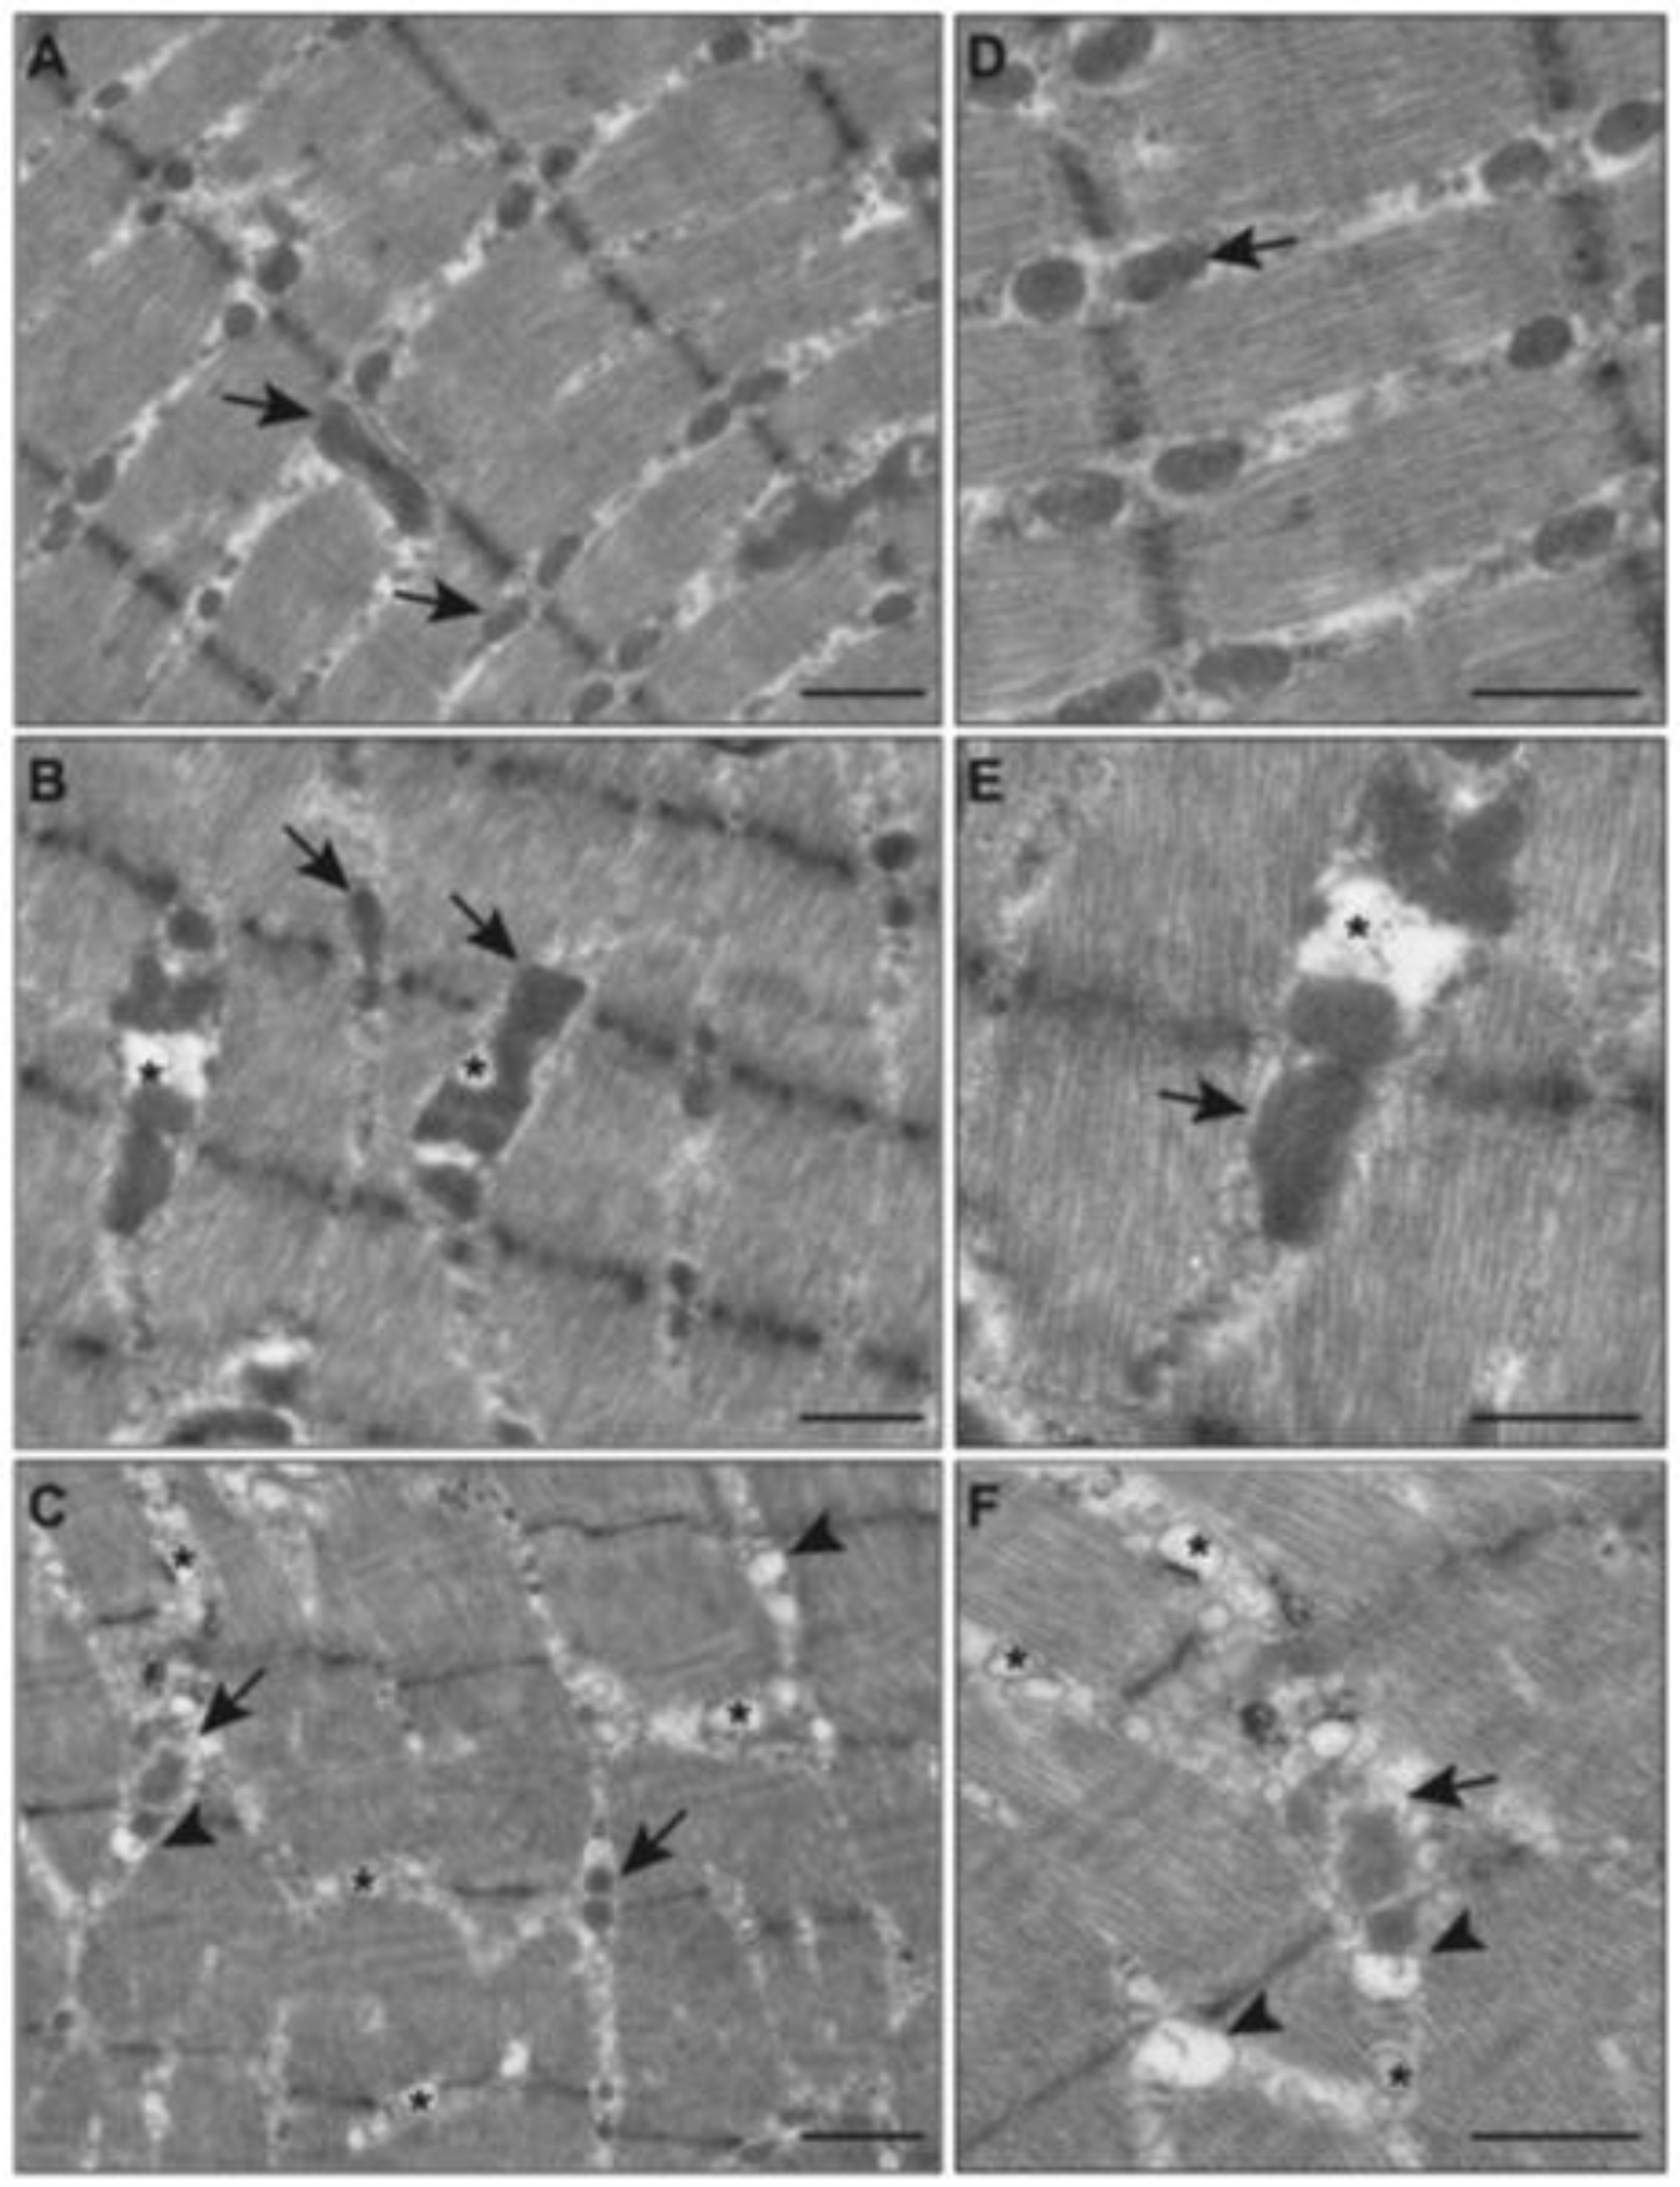

2.5. Effects of E-Cig on Mitochondrial Morphology (TEM)